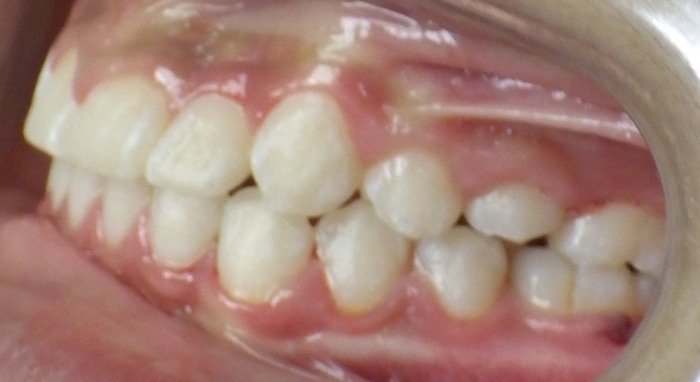

Christopher was a Phase I case that presented with a Class III bite on the right side and around a 90 degree rotation of his upper right central and lateral incisors. During Phase I we placed upper 2×4 brackets (brackets on upper 4 front permanent teeth) since he still had several primary teeth left. We began Phase II and at this time Christopher had 5 mm of upper crowding and 3 mm of lower crowding. We placed brackets on the upper and lower arches and had him wear elastics during treatment. Christopher ended with a really beautiful Class I bite and smile.